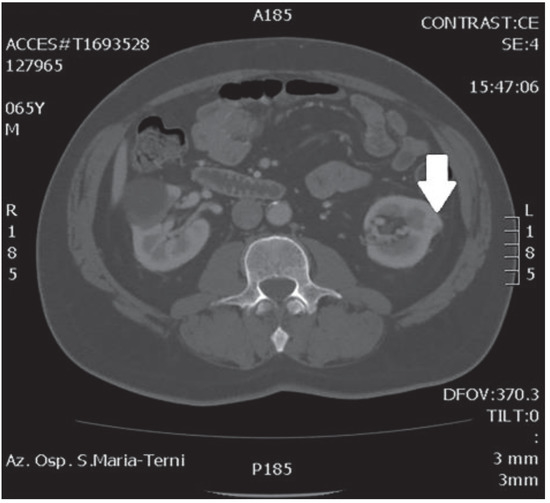

In October 2018, a 66-year-old man with hypertension and no significant prior surgical history showed a serum PSA level of 4.5 ng/mL. At clinical stage T1c, Gleason score 6 (3 + 3) PCa was diagnosed in 11 out of 22 core biopsies, all in the right side of the gland. A total body bone scan was negative for metastasis. An abdominal CT scan showed no evidence of pathologic pelvic lymphadenectomy but highlighted two incidental heterogeneous enhancing solid masses in the left kidney that were suspicious for renal cell carcinoma: one sized 32 mm in the lower pole and the second of 10 mm in the mesorenal site. A 6-cm asymptomatic simple cyst was found in contralateral kidney. Serum creatinine was 1.43 mg/dL. CT imaging of renal masses is shown in Figure 1 and Figure 2.

Figure 2.

Renal mass of the lower pole.